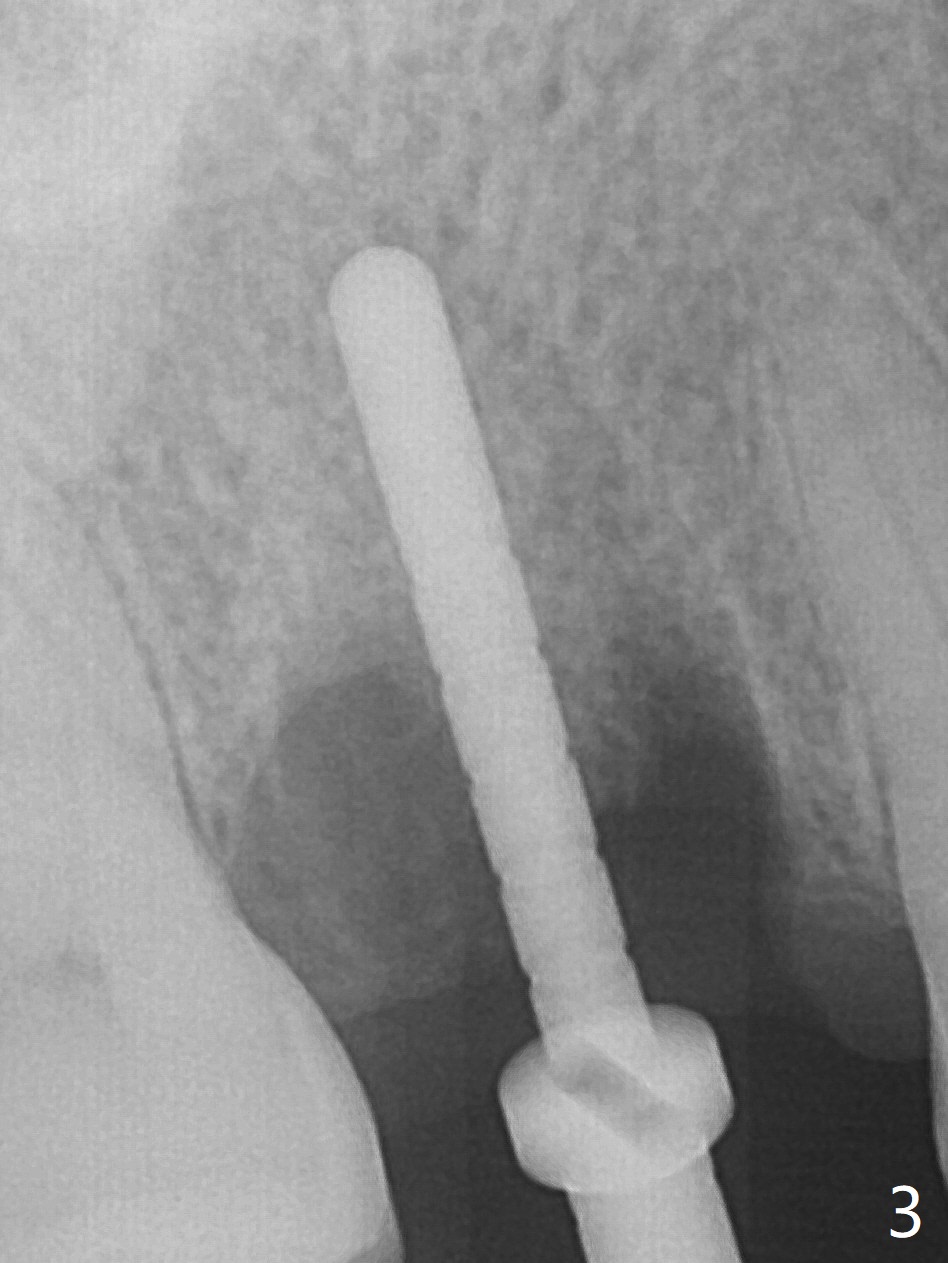

While the tooth #3 has a mesiodistal crack line, etiology may be due to chronic periodontitis with bruxism. After extraction, there is granulation tissue attached to the distobuccal (DB) root. The DB socket is larger than the mesiobuccal one (Fig.1). Osteotomy is initiated in the DB slope of the septum for 10 mm (Fig.2,3). Since there is ample apical bone, the depth of the osteotomy increases to 11.5 mm. When a 5x10 mm dummy implant is placed, primary stability is satisfactory (Fig.4 (yellow line: apical space)). The definitive implant remains the same dimension with deeper placement (Fig.5,6 (~ 20 Ncm)); with placement of a 6.5x4(3) mm abutment and Vanilla/Osteogen Graft (*), an immediate provisional is fabricated in place (without taking out for trimming) with sufficient clearance with the opposing dentition. It appears that the moderately long implant (10 mm) is able to achieve primary stability for immediate placement. When the provisional is removed 2 months postop, bone graft seems to be adhered to the socket (Fig.7). To improve local hygiene, the provisional does not return. The implant seems to have osteointegrated 3.5 months postop (Fig.8). The crown/abutment is loose approximately 1 year post cementation. Due to her daughter's contracting COVID 19, she postpones returning for approximately 1 year. The access hole is opened, crown/abutment (6.5x4(4) mm) removed, proximal contacts reduced, crown/abutment reseated without certainty. BW shows incomplete seating probably due to bony interference (Fig.9). A 5.5x4(4) mm can not be seated (bouncing, probably due to soft tissue interference). When a 4.5x5(4) mm abutment (UF) is seated, hand tightening is smooth, confirmed by BW (Fig.10). Two weeks later, the new crown is cemented intraorally. The crown/abutment is removed for cleaning. The abutment screw is torqued at 20 NCM.